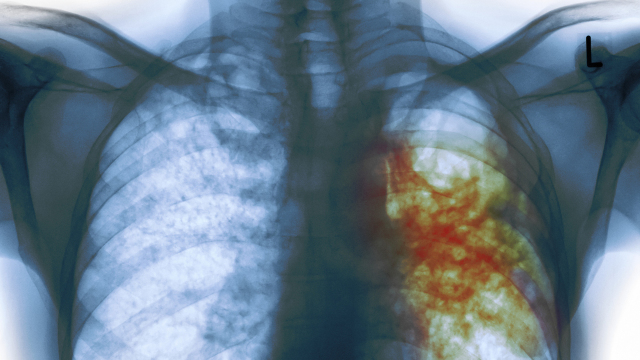

MSRA (methicillin-resistant Staphylococcus aureus), for example, is a life-threatening bacteria that can spread fast in hospitals and has the property…

The reckless and unprecedented overuse of antibiotics worldwide has contributed to the emergence of antibiotic-resistant bacteria, the so-called superbugs. At…